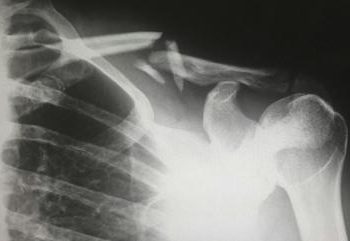

Periartrite spalla

La periartrite scapolo-omerale è una condizione dolorosa che colpisce la spalla, coinvolgendo principalmente i tessuti molli intorno all’articolazione scapolo-omerale, come tendini, legamenti e borse. È spesso conosciuta anche come sindrome della spalla dolorosa o spalla congelata quando è particolarmente severa. ...